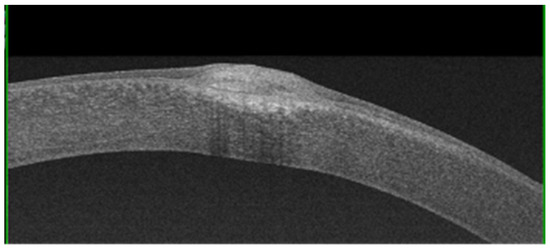

AS-OCT can be used to evaluate the morphological characteristics and depth of nodules, as well as their adherence to the underlying planes, in order to take decisive therapeutic choices [12,13]. AS-OCT can show some nodules with triangular spicules that protrude into the underlying space, and they are occasionally shown with a stromal scarring below the Bowman’s membrane.

Additionally, AS-OCT evaluation has proven effective in differential diagnoses with monolateral squamous neoplasia of the ocular surface and in addressing the correct therapeutic approach [14].AS-OCT shows coalescent subepithelial deposits with a variable and heterogeneous signal intensity, probably due to density fluctuations (Figure 5). The nodules are overlaid by a thinned epithelium. A structural and ultrastructural analysis of the corneal epithelium showed dramatic changes; indeed, a reduction in its height, particularly above the nodule in advanced stages, was demonstrated [15].

Figure 5. A nodule imaged via AS-OCT showing hyper-reflective deposits located under the epithelium and extending into the anterior stroma.